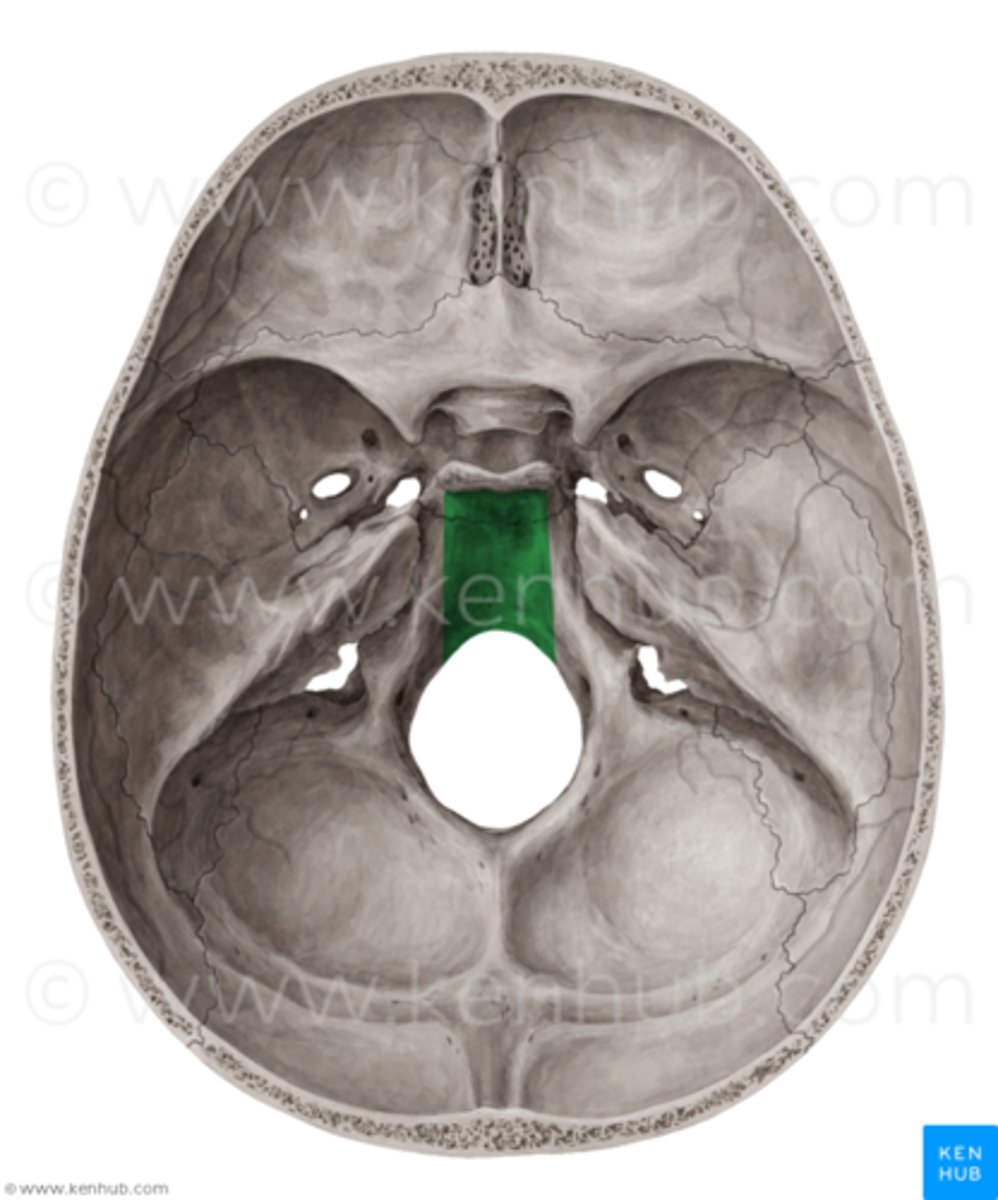

Name this bony landmark.

sella turcica

tuberculum sellae

dorsum sellae

posterior clinoid processes

clivus